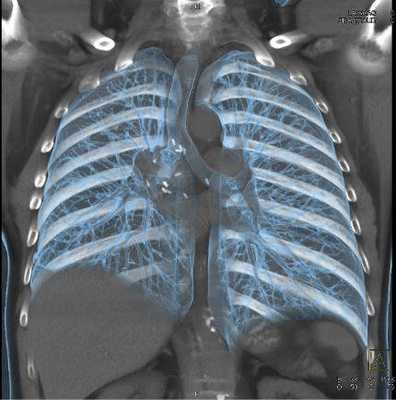

КТ органов грудной клетки - усовершенствованный способ рентгенографической визуализации, который использует излучение для создания детальных изображений грудины, грудино-ключичных суставов, ребер, прилежащих мягких тканей и органов (в первую очередь, легких).

Исследование проводят, если после выполненной обычной рентгенографии причина жалоб осталась неясной или есть подозрение на патологический процесс в данной области. Компьютерная томография органов грудной клетки может быть выполнена в качестве альтернативы МРТ, если у пациента есть противопоказания к проведению магнитно-резонансного сканирования. Для лучшей визуализации возможно введение контрастного вещества. Основным преимуществом КТ является его способность одновременно демонстрировать кости, мягкие ткани (при контрастировании) и кровеносные сосуды.Что показывает КТ грудной клетки

![Мультиспиральная КТ грудной клетки, 3D-реконструкция]()

Мультиспиральная КТ грудной клетки, 3D-реконструкция

Специалисты выделяют в средостении три области: центральное (сосудистое пространство с перикардом и его содержимым, сосудами и лимфатическими узлами), переднее (жировая клетчатка, вилочковая железа, внутренние грудные артерии и лимфоидные ткани) и заднее (трахея, пищевод, нисходящая часть грудной аорты, лимфоузлы и паравертебральные пространства грудной клетки). Соответственно, все патологические процессы, которые протекают в данных зонах, могут быть видны.